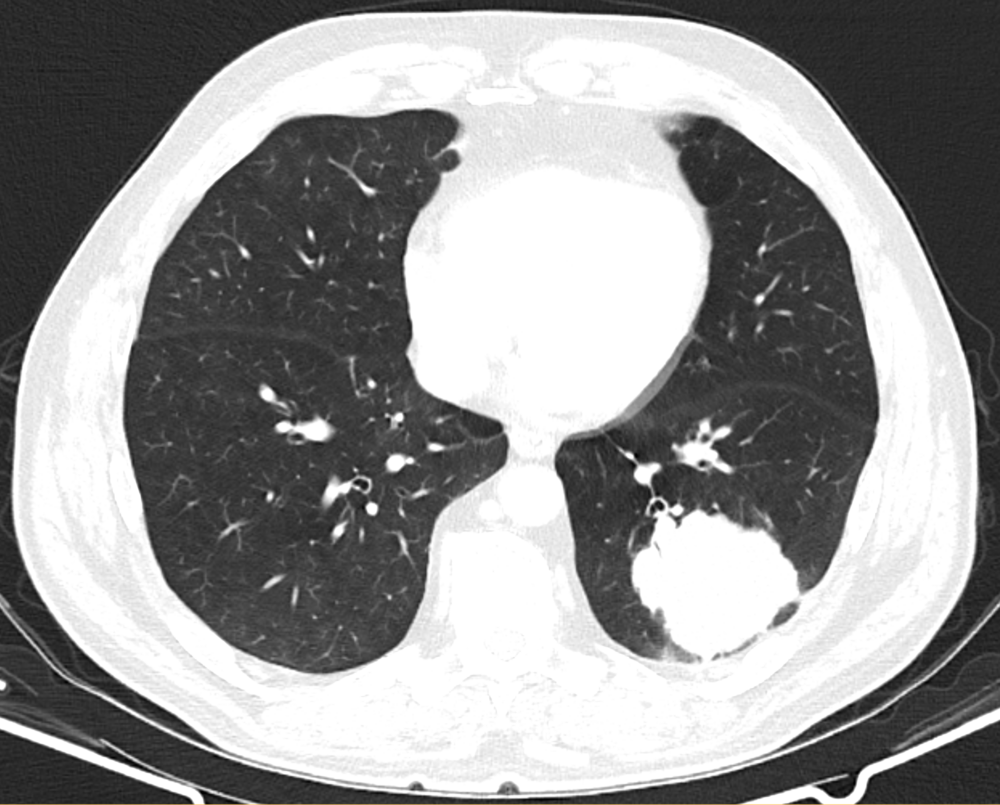

Hochauflösendes CT der Lunge

Unser hochauflösendes CT der Lunge ermöglicht eine präzise Darstellung der Lunge und ihrer kleinsten Strukturen, wie Bronchien und Lungenbläschen (Alveolen). Das Verfahren dient der Diagnose und Überwachung verschiedener Lungenkrankheiten wie Lungenentzündung, Lungenfibrose, Lungenkrebs, Bronchiektasen und anderer Atemwegserkrankungen. In einigen Fällen setzen wir während der CT-Untersuchung Kontrastmittel ein, um bestimmte Lungenanomalien besser sichtbar zu machen. Die hochauflösenden Querschnittsbilder der Lunge ermöglichen dem Arzt eine genaue Beurteilung von Lungenerkrankungen in einem frühen Stadium. Dies ist entscheidend für eine frühzeitige Diagnose und eine effektive Behandlung.